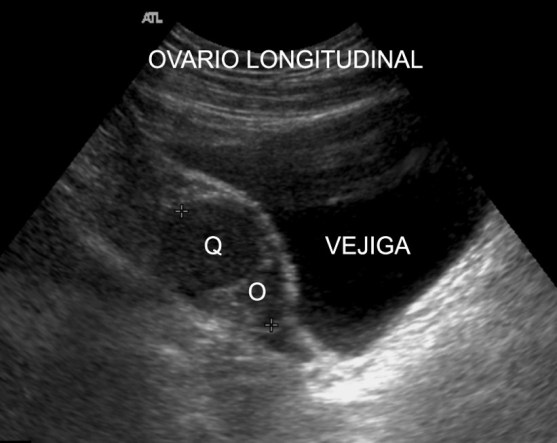

Quiste hemorrágico típico en un ovario,marcado con la Q. Aspecto hipoecogénico.